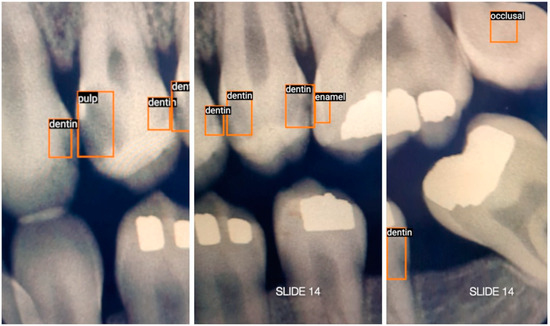

英文标题: Real-Time Caries Detection of Bitewing Radiographs Using a Mobile Phone and an Artificial Neural Network: A Pilot Study

中文标题:基于手机与人工神经网络的咬翼片实时龋齿检测:一项初步研究

文章链接:https://www.mdpi.com/2673-6373/3/3/35

英文标题: One-Stage Methods of Computer Vision Object Detection to Classify Carious Lesions from Smartphone Imaging

中文标题: 基于单阶段计算机视觉目标检测的智能手机影像龋损识别方法

文章链接:https://www.mdpi.com/2673-6373/3/2/16